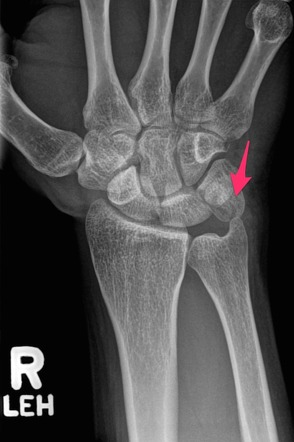

Perilunat çıkık nedeniyle tedavi edilen hastada trikuetro-pisiform eklemdeki yaralanma ve pisiformun minik parçalı kırıkları görülmekte. Pisiform kırıkları, ağırlıklı olarak konservatif yöntemlerle tedavi edilir.

Özellikle ayrışmamış akut kırıklara 3–6 haftalık alçı uygulanır. Ayrışmış kırıklarda vida ile osteosentez mümkündür.

Parçalı kırıklar ve semptom veren kaynamamalar ise pisiformun çıkarılması ile tedavi edilir. Hamatum çengelinin çıkarılmasında olduğu gibi, yakın komşuluğundaki ulnar damar sinir paketine dikkat edilmelidir

Düz radyografi; Bazıları düz filmde gizli olabilir. Pisotriquetral eklem en iyi 30 derece supinasyonlu lateral görünümde veya karpal tünel görünümü kullanılarak görülebilir .